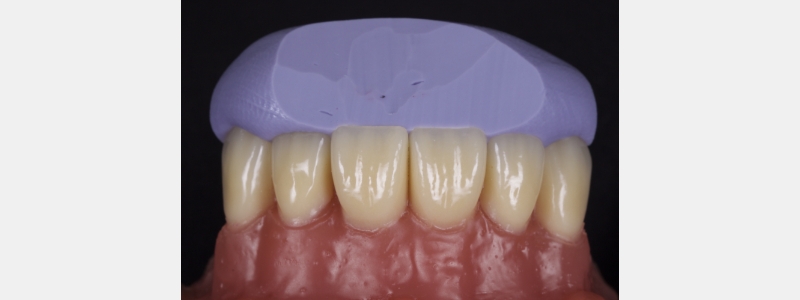

In this case, a young patient in his early 20s presents with discolored central incisors, multiple diastemas, and a canted incisal plane (Fig. 23).

The esthetics were assessed by the patient, and some adjustments were made to the distal line angles of the lateral incisors. When the patient was satisfied with the appearance, another sectional digital scan of the modified mock-up in the patient’s mouth was taken and stitched into the original scan to form the final mock-up (Figs. 25 and 26).